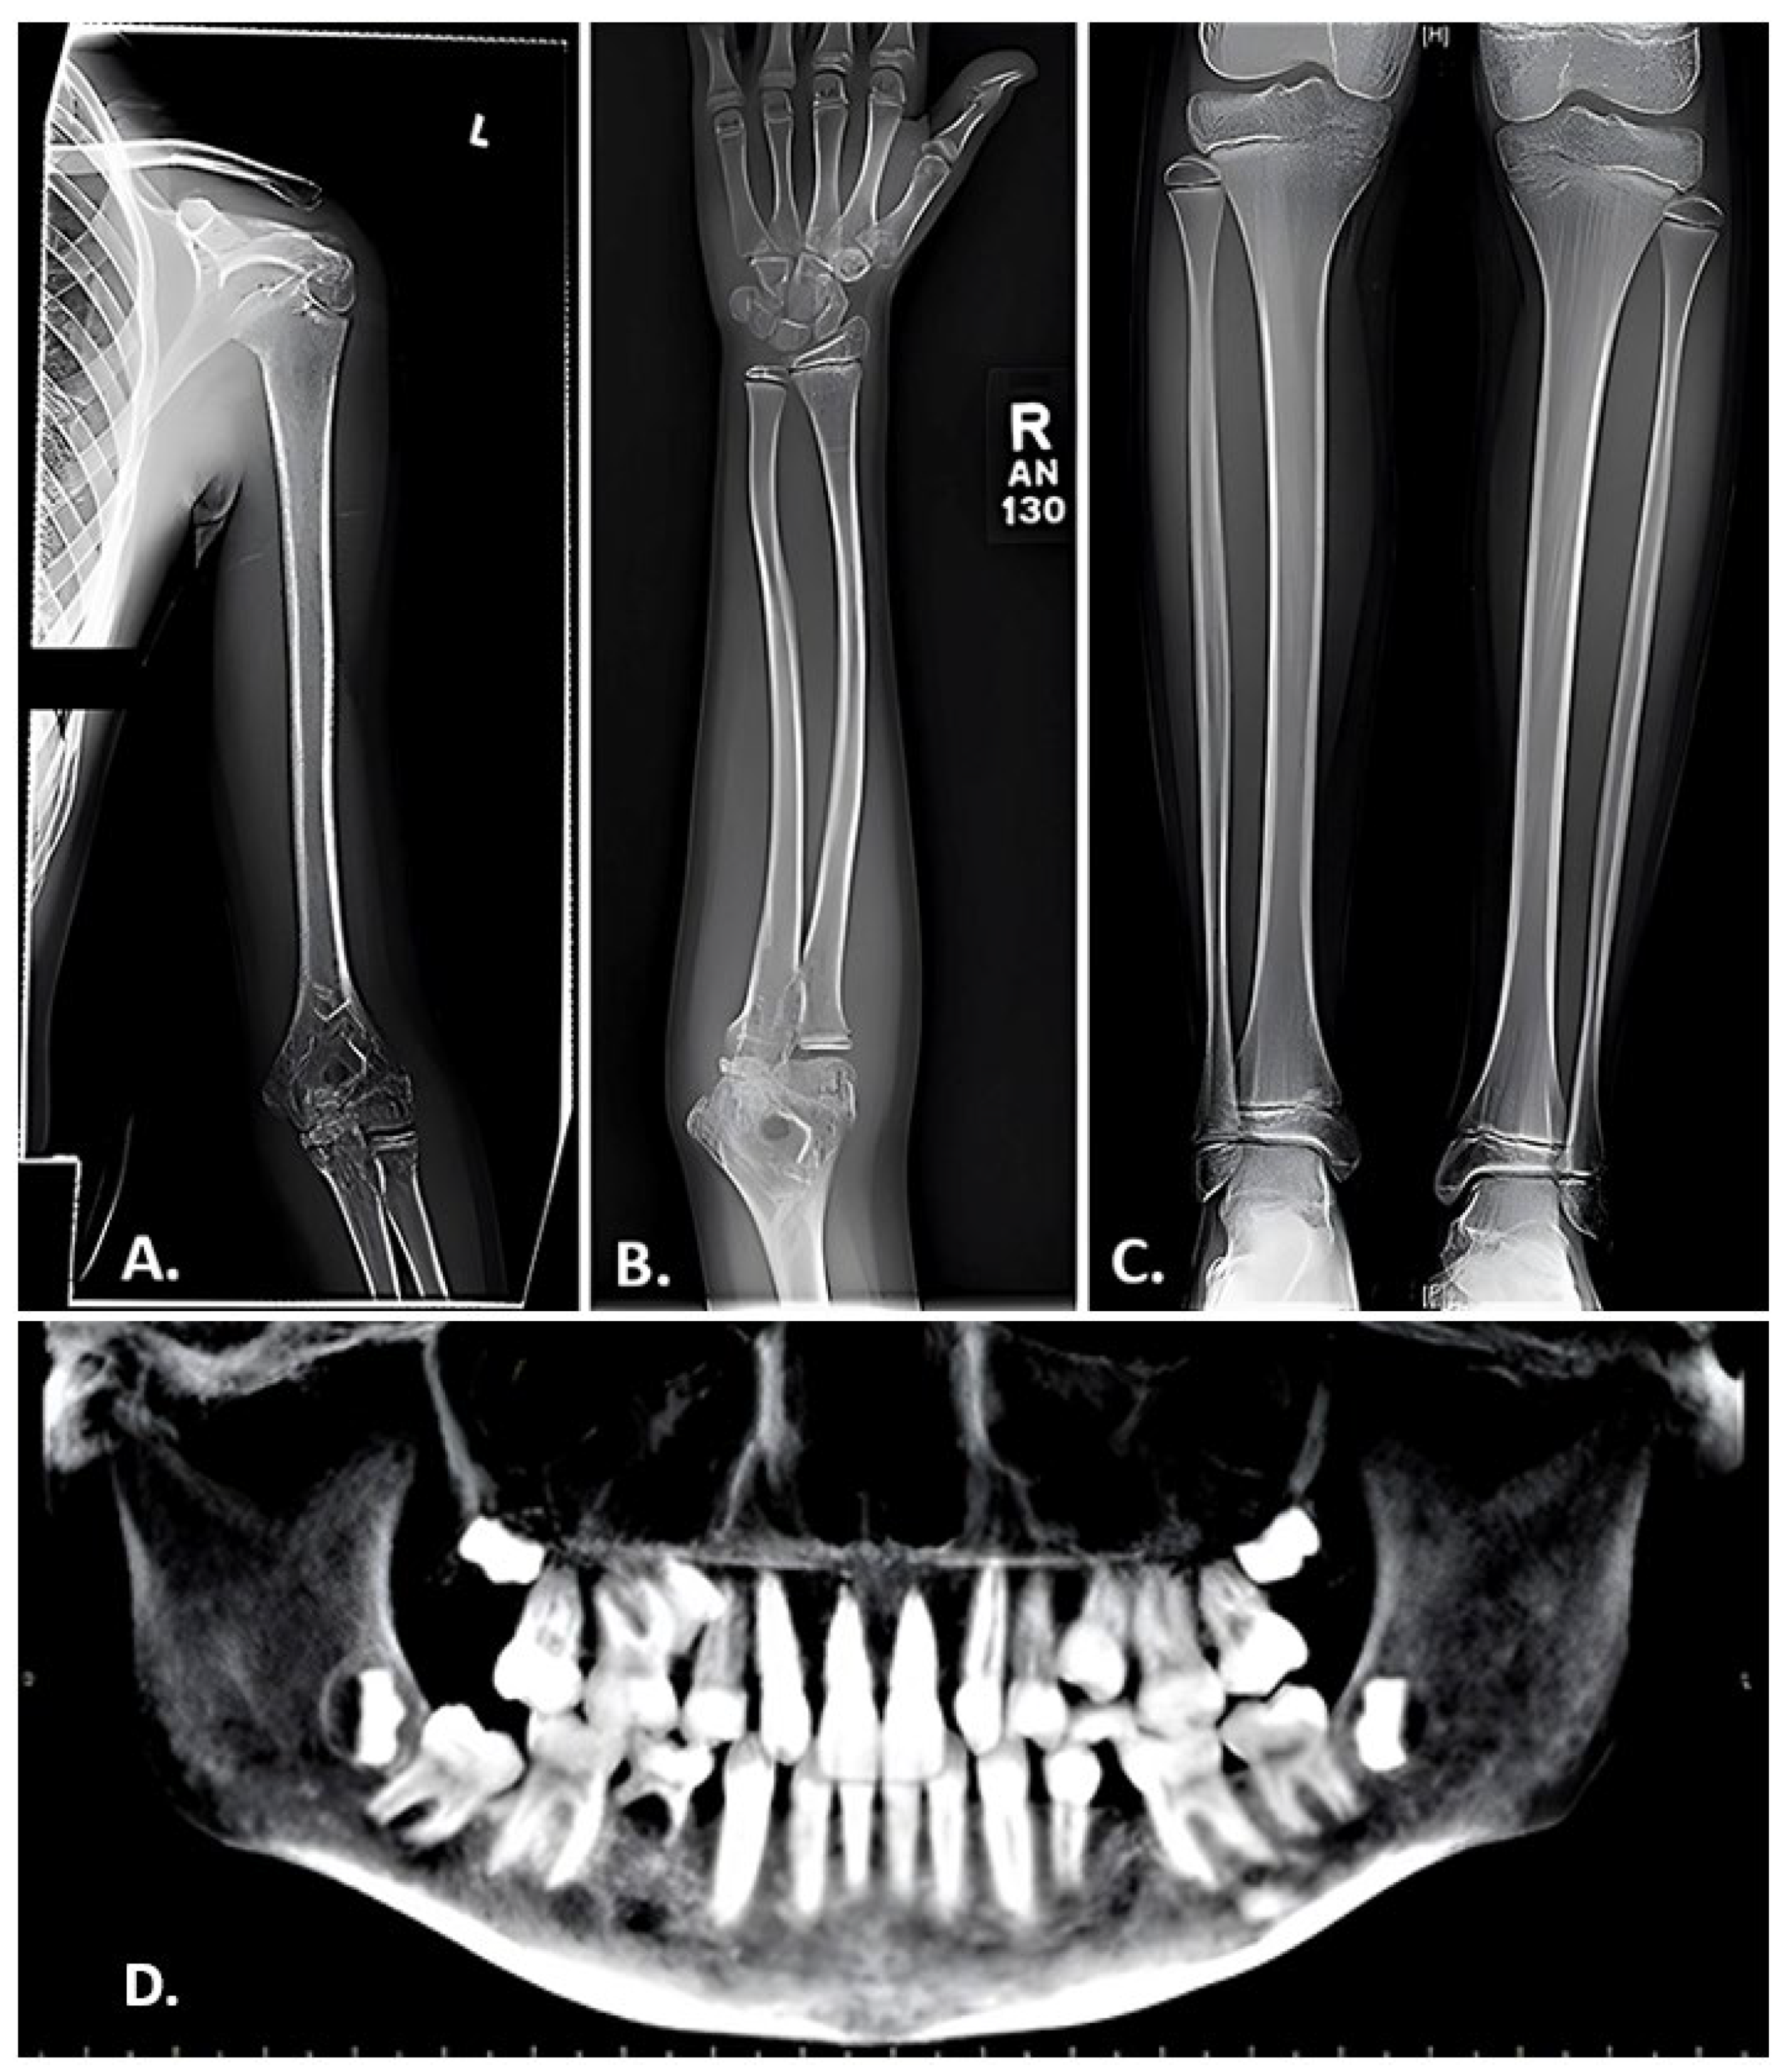

- Karakilic-Ozturan, E.; Altunoglu, U.; Ozturk, A.P.; Al, A.D.K.; Abali, Z.Y.; Avci, S.; Wollnik, B.; Poyrazoglu, S.; Bas, F.; Uyguner, Z.O.; et al. Evaluation of growth, puberty, osteoporosis, and the response to long-term bisphosphonate therapy in four patients with osteoporosis-pseudoglioma syndrome. Am. J. Med. Genet. A 2022, 188, 2061–2070. [Google Scholar] [CrossRef] [PubMed]

- Heidari, A.; Homaei, A.; Saffari, F. Novel Homozygous Nonsense Mutation in LRP5 Gene in Two Siblings with Osteoporosis-pseudoglioma Syndrome. J. Clin. Res. Pediatr. Endocrinol. 2021. ahead of print. [Google Scholar] [CrossRef] [PubMed]

- Abdel-Hamid, M.S.; Elhossini, R.M.; Otaify, G.A.; Abdel-Ghafar, S.F.; Aglan, M.S. Osteoporosis-pseudoglioma syndrome in four new patients: Identification of two novel LRP5 variants and insights on patients’ management using bisphosphonates therapy. Osteoporos. Int. 2022, 33, 1501–1510. [Google Scholar] [CrossRef]